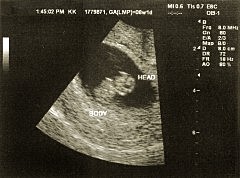

Sexto mes

Ahora el feto mide entre 28 y 36 cm., pesa aproximadamente 1 kg. Su cerebro continúa creciendo rápidamente y sus movimientos se vuelven más rápidos. Ya tiene papilas gustativas, por lo que puede diferenciar los sabores cuando se alimenta a través del líquido amniótico. Su piel está arrugada y es tan delgada que se pueden ver sus vasos capilares, sin embargo ya tiene pelo en su cabeza e incluso cejas y pestañas. Sus órganos continúan madurando y sus pulmones aún no funcionan plenamente.

Séptimo mes

Ahora ya pesa 1.1 kg aproximadamente. Sus órganos siguen madurando, sus huesos ya están desarrollados pero son suaves y su piel deja de ser transparente y arrugada gracias a la grasa acumulada. Ahora ya realiza muchos movimientos y estos son cada vez más complejos: abre y cierra los ojos, se chupa el pulgar, patea y se estira; además sus sentidos también se han desarrollado por lo que es más sensible a la luz y los sonidos externos.